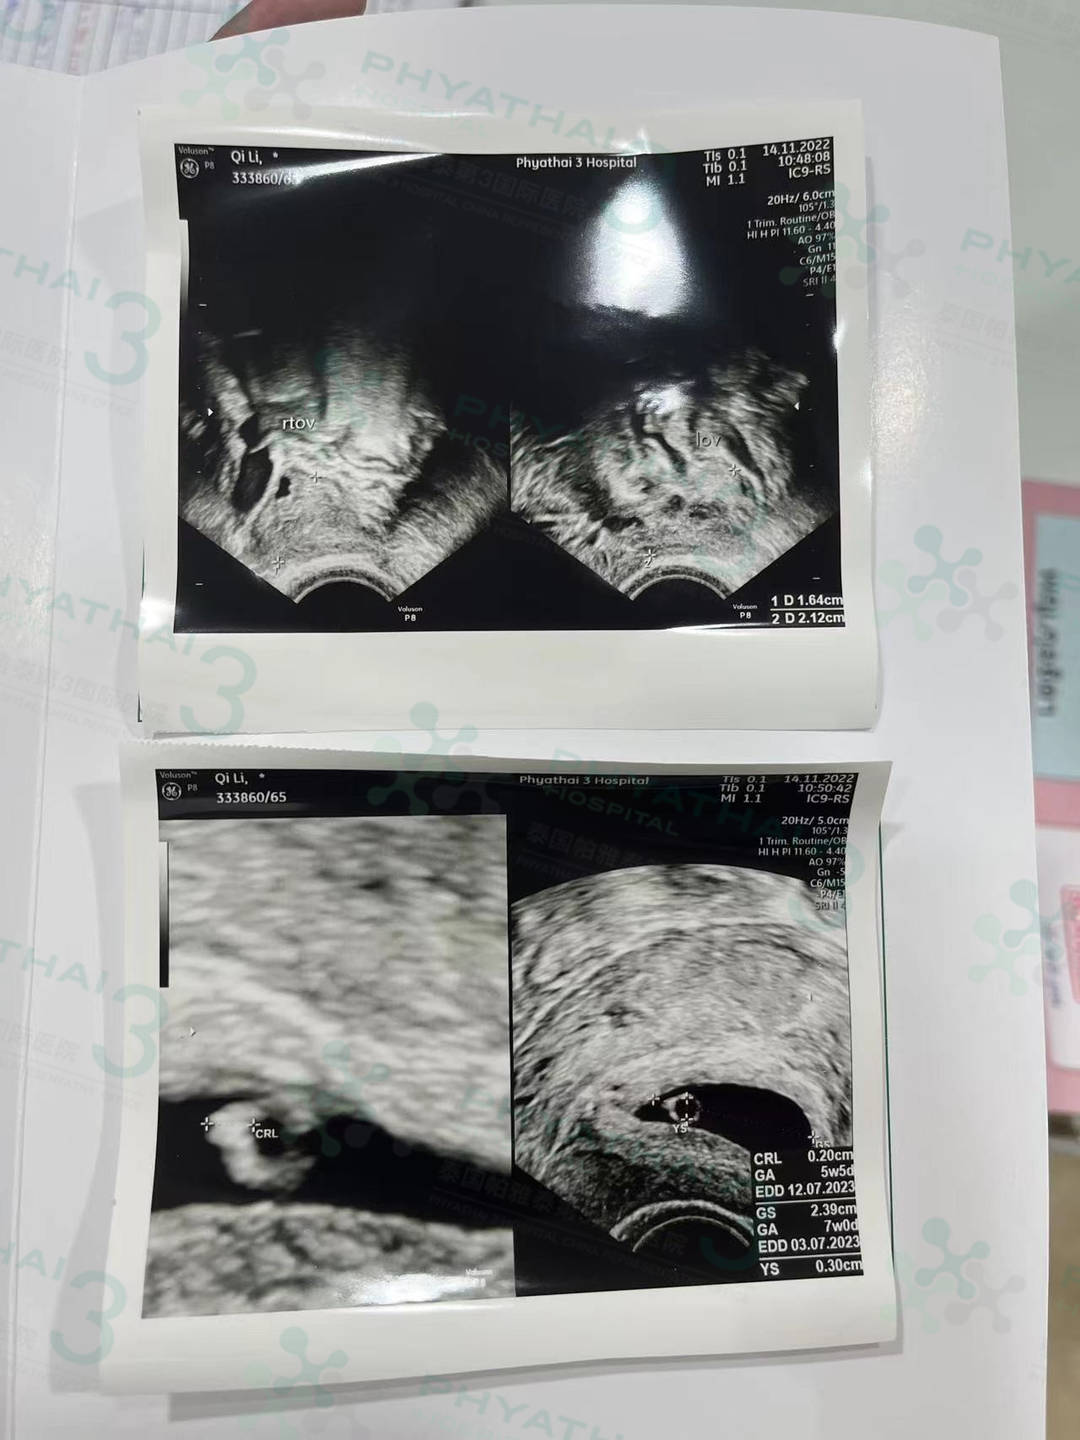

:提前顺利的带小王子回国啦 女士验孕成功,血值翻倍。今天女士孕期6周,按照医生预约来监测平躺着床情况。当阴超...